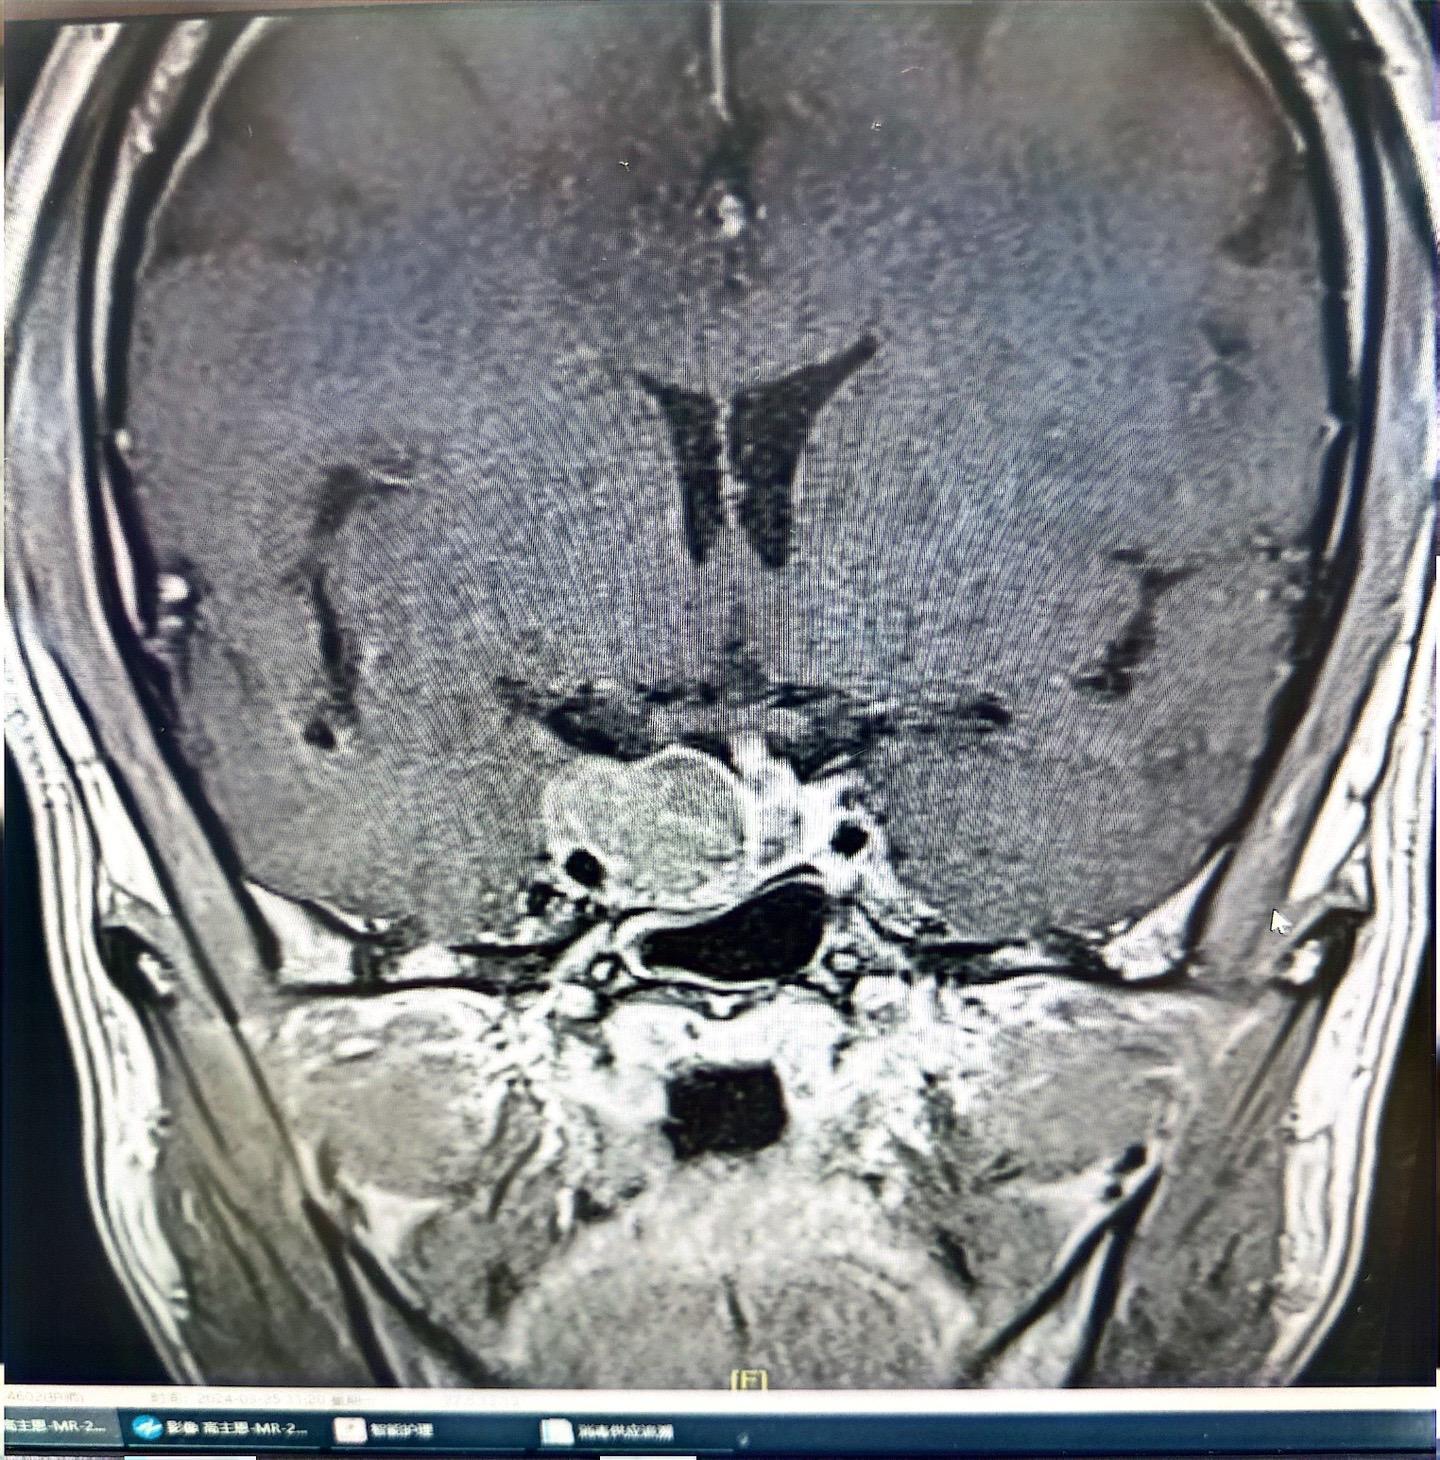

垂体瘤(生长激素型)分泌型垂体肿瘤难度还是较大,经鼻子手术,双镜联合,同时术中磁共振辅助,术后生长激素终于恢复正常!